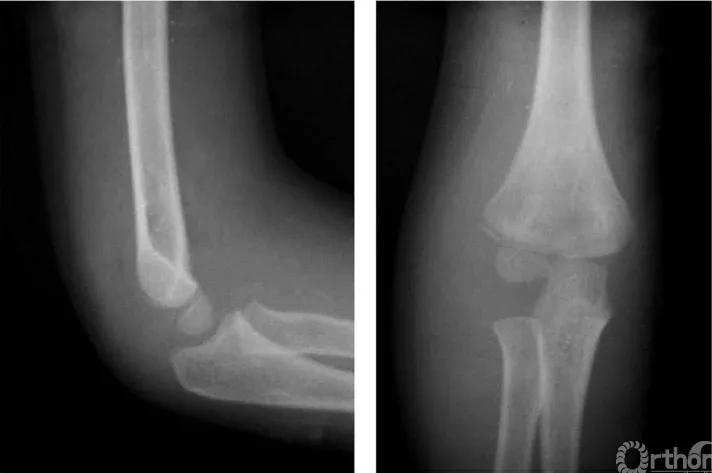

一、无移位型

例:仅见骨折线通过干骺端(图1)。

图1